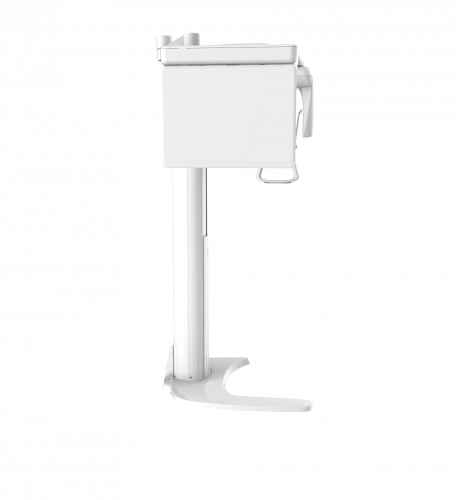

| TYPE | TOP VIEW | FRONT VIEW |

|---|---|---|

|

PaX-i (Pano) |

|

|

|

PaX-i SC (Pano/Scan Ceph) |

|

|